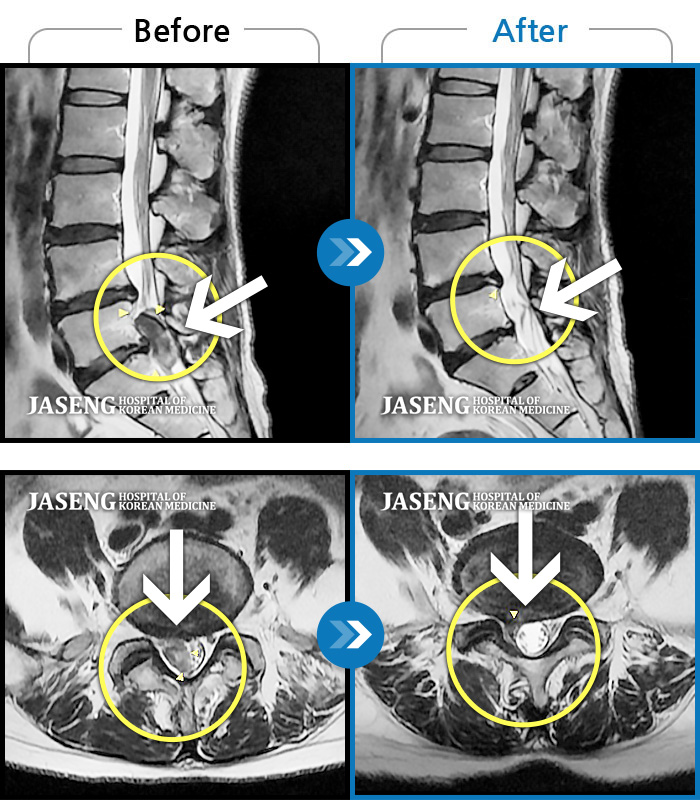

허리디스크

해운대 · 이상건 원장

허리디스크로 인한 요통

촬영시기

2018.04.21 ~ 2018.11.10

2019.01.04

조회수 244